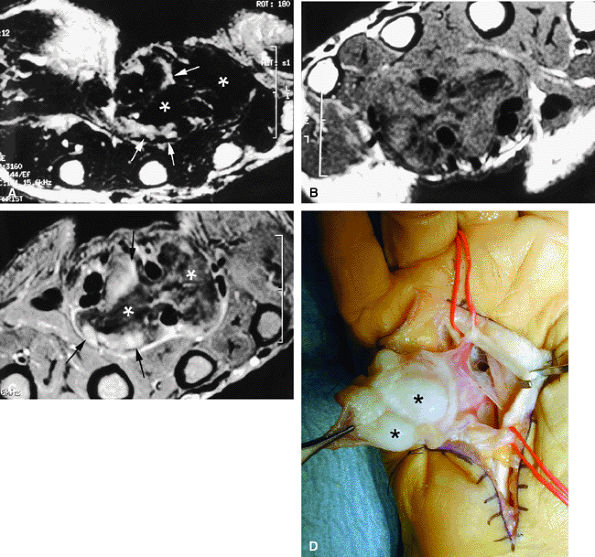

FIGURE 11.70 ● Chondromatosis of the sheath of the flexor tendons on (A) an axial fast spin-echo T2-weighted image and T1-weighted images before (B) and after (C) injection of gadolinium with fat suppression. There is enlargement of the tendon sheaths of the third and fourth fingers with synovitis (arrows) and cartilage signal characteristics (asterisks). (D) Surgical exposure indicating white cartilage nodules (asterisks).

|